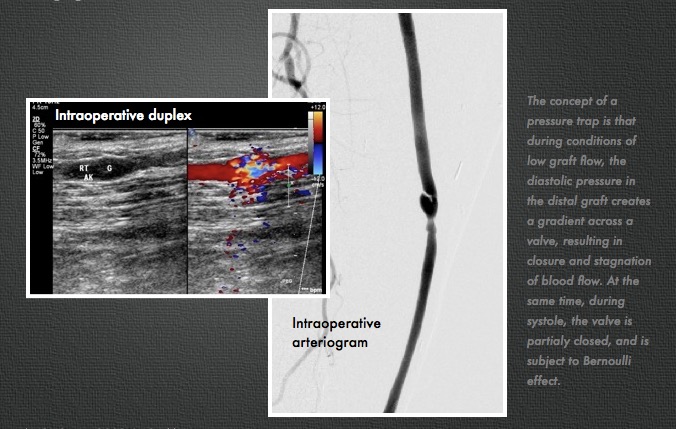

I took him to the operative endovascular suite, and arteriography showed a severe stenosis (image above, right) due to a hypertrophied valve. .

The concept of a pressure trap is that during conditions of low graft flow, the diastolic pressure in the distal graft creates a gradient across a valve, resulting in closure and stagnation of blood flow. At the same time, at the onset of systole, the valve is partialy closed, and is subject to Bernoulli effect.

Robiscek et al [ref 3] performed intraoperative flow studies and found that under conditions of low graft flow, pressure traps occurred in reversed vein grafts. When diastolic pressure in the vein segment distal to the valve is greater than the systemic diastolic pressure, the valve closes.

This patient does have sluggish outflow due to tibial arteries that are severely disease. I believe this causes a pressure trap, but I don’t believe it is a sufficient condition for development of valvular hypertropy resulting in a stenosis.